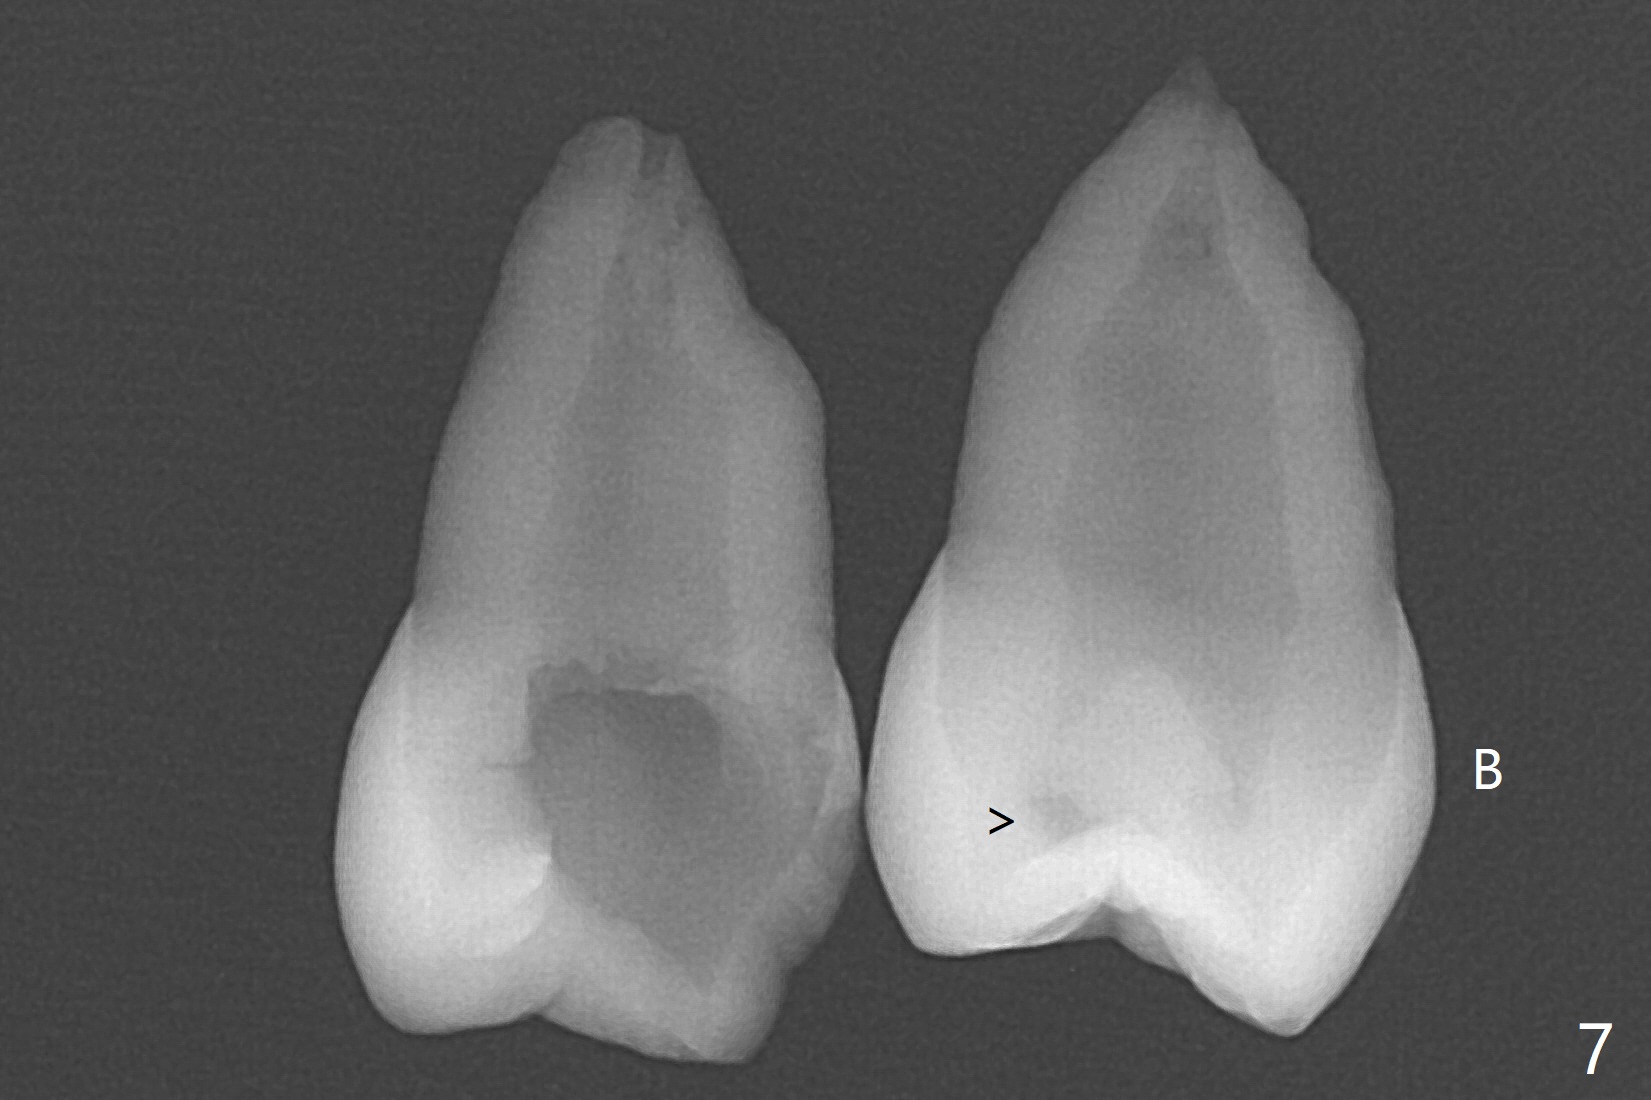

A 14-year-old woman with crowding returns to clinic for extraction of the 1st bicuspids. Orthodontic treatment has started partially. Because of severe caries at UR5 (Fig.1 *), BWs and PA are taken, which reveal DO incipient caries at UL, LL5 (Fig.2) and large PARL at UR5 (Fig.3 *). Upon receiving a revised treatment plan, four of 2nd bicuspids are extracted. The large PARL is confirmed intraop. Examination of the extracted teeth shows mesial caries at UL5, which is not detected by X-ray (Fig.4 <). By comparison, DL caries of UL5 is more severe (Fig.5). Check the neighboring teeth for caries when the patient returns for recall. The pulpal exposure of UR5 is large (Fig.6). So is the pulpal chamber (Fig.7). The large canal (Fig.7) in fact consists of 2 ones (Fig.11 red arrows) with a separation in between (*). The DL caries at LL5 is at the stage of decalcification (Fig.8), not visible in X-ray (Fig.12, as compared to Fig.7 >).